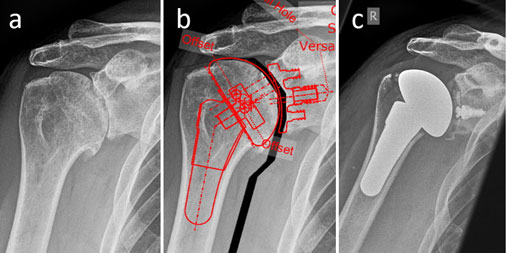

Fallbeispiel – 56-jähriger Patient mit fortgeschrittener Schultergelenksarthrose rechts wurde mittels anatomischer Totalendoprothese versorgt: präoperatives Bild mit fortgeschrittener Destruktion der Gelenkfläche (a), digitale präoperative Planung der exakten Größe und Positionierung der Implantate (b) und postoperatives Röntgenbild (c).